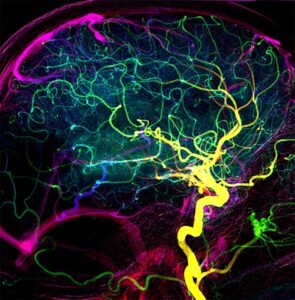

Arterienverbindungen beeinflussen Therapieerfolg nach einem Schlaganfall27. Februar 2024 Darstellung der Blutgefäße im Gehirn eines Patienten ohne frühe venöse Füllung. (Quelle: © P. Thurner und Z. Kulcsar | Universitätsspital Zürich) Blutgefäße, die benachbarte Arterienbäume miteinander verbinden, regulieren die Wiederdurchblutung des Gehirns nach einem Schlaganfall. Wie Forschende der UZH zeigen, verhindern sie, dass es nach der Entfernung eines Blutgerinnsels zu Hirnblutungen kommt. Damit spielen sie eine entscheidende Rolle bei der Erholung von Patientinnen und Patienten. Um die Auswirkungen eines ischämischen Schlaganfalls so gering wie möglich zu halten, muss das verstopfte Gefäß wieder geöffnet werden. Dies geschieht medikamentös oder mithilfe eines Katheters. Doch selbst wenn das Gerinnsel rechtzeitig entfernt wird, erholen sich viele Schlaganfallpatienten nur schlecht. Die Forschungsgruppe von Susanne Wegener, Professorin an der Universität Zürich (UZH) und leitende Ärztin an der Klinik für Neurologie des Universitätsspitals Zürich (USZ), zeigt nun, dass der Erfolg der Schlaganfallbehandlung vom Kollateral-Netzwerk abhängt. Kollateralen sind Blutgefäße, die benachbarte Arterienbäume miteinander verbinden und als potenzielle Umleitungen im Falle einer Gefäßverstopfung fungieren. „Diese Gefäßbrücken erhalten die Selbstregulierung des Gehirns aufrecht und ermöglichen eine langsamere, allmähliche Wiederdurchblutung, was zu kleineren Infarkten führt“, sagt Wegener. Überschießende Wiederdurchblutung erhöht Sterblichkeit Für seine Arbeit verwendete das Forscherteam um die beiden Erstautoren Nadine Binder und Mohamad El Amki ein Mausmodell für Schlaganfälle sowie mehrere moderne Bildgebungsverfahren, um Veränderungen in der arteriellen Blutzufuhr am lebenden Organismus zu untersuchen. Bei Versuchstieren, die über schlechte Kollateralen verfügten, waren die Arteriensegmente nach der Gerinnselentfernung dysfunktional und starr. „Die darauffolgende übermäßige Wiederdurchblutung führte bei den Mäusen zu Blutungen und einer erhöhten Sterblichkeit“, erklärte Wegener. Darstellung der Blutgefäße im Gehirn eines Patienten mit früher venöser Füllung. (Quelle: © P. Thurner und Z. Kulcsar | Universitätsspital Zürich) Die Ergebnisse aus dem Mausmodell konnten die Forschenden anschließend auch bei Schlaganfallbetroffenen bestätigen: Patienten mit schlechten Kollateralen zeigten nach erfolgter Öffnung des verstopften Blutgefäßes eine ähnlich schnelle und übermäßige Wiederdurchblutung des Hirnareals wie die Mäuse. Auch bei ihnen kam es zu kleinen Blutungen im Gehirn, und ihre Genesung war schlechter. Je besser die Arterienverbindungen, desto besser die Erholung Bisher stand die schnelle Entfernung des Gerinnsels bei Patienten mit Schlaganfall im Vordergrund. Die Probleme durch zu schnelle Wiederdurchblutung nach der Therapie und ihre potenziell schädlichen Auswirkungen bei Schlaganfallpatienten wurden bislang allerdings kaum beachtet. Nun ist es möglich, Schlaganfallpatienten mit erhöhtem Risiko während der Entfernung des Blutgerinnsels anhand der Geschwindigkeit der Wiederdurchblutung zu identifizieren. „Künftige therapeutische Maßnahmen sollten darauf abzielen, die Funktion der Gefäßbrücken zu verbessern, um eine günstige, graduelle Wiederdurchblutung nach dem Schlaganfall zu ermöglichen“, lautet Wegeners Fazit.